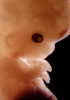

Carnegie Stage 22 (54 post-ovulatory days)

Most embryos at stage 22 are approximately 54 postovulatory days old and measure 25-27 mm in length. Distinguishing criteria for this stage include clear formation of the external ear, the hands begin to extend ventrally beyond the body wall, the fingers of one hand may overlap the fingers of the opposite hand, thickened eyelids just begin to cover the outer margins of the eye, and the superficial vascular plexus of the head now extends about three-quarters of the way above the eye-ear level.